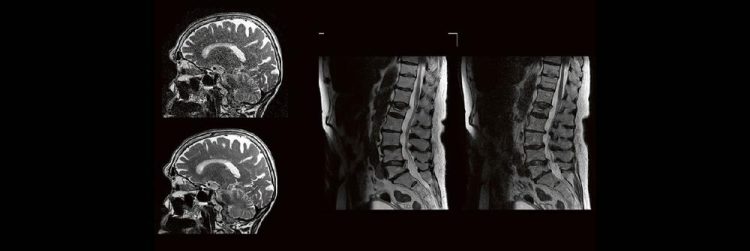

Outside the box-Vortrag: die Neuroradiologie der Moral (Webinar | Online)

Professor Dr. med. Michael Knauth Das Treffen moralischer Entscheidungen erfordert – wie jede andere Hirnleistung auch – das Zusammenwirken verschiedener Hirnareale. Der Vortrag nimmt auf eine interaktive Reise durch die Mehrzügeligkeit moralischer Entscheidungen (emotional vs. utilitaristisch) und gängiger moralischer Dilemmata (Trolley-Problem) und führt schließlich zu den mit dem Treffen dieser Entscheidungen befassten Hirnregionen und zu…Continue reading Outside the box-Vortrag: die Neuroradiologie der Moral (Webinar | Online)